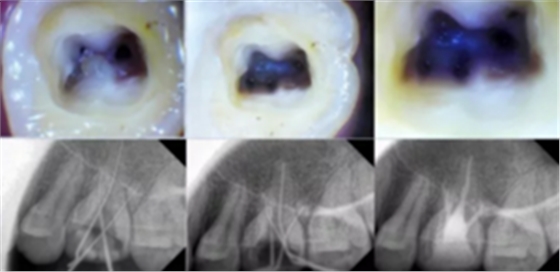

開髓去腐質(zhì)

根管治療開髓前必須去凈腐質(zhì),然后換用另一根新的車針(裂鉆或金剛砂車針均可,但金剛砂車針開髓震動感少,開髓穩(wěn))進(jìn)入髓腔,穿通髓腔后換高速球鉆揭頂,揭頂一定要全,以能看清整個髓室底為準(zhǔn),然后換用裂鉆或金剛砂車針修整髓壁。

這一步質(zhì)控的標(biāo)準(zhǔn)是:

①去凈腐質(zhì)和原有充填物。

②揭凈髓頂,看到整個髓底解剖結(jié)構(gòu)。

③髓壁與根管壁連續(xù)流暢。

④沒有牙頸部臺階,沒有過度切割髓壁和髓底。

共有 4 張 X 線片,分別是術(shù)前、診斷絲 、主牙膠尖確認(rèn)、術(shù)后。

( 1 )術(shù)前:術(shù)前 X 線片用來了解牙齒的大概情況。術(shù)前預(yù)期為多根牙時 X 線片應(yīng)偏頭拍攝。